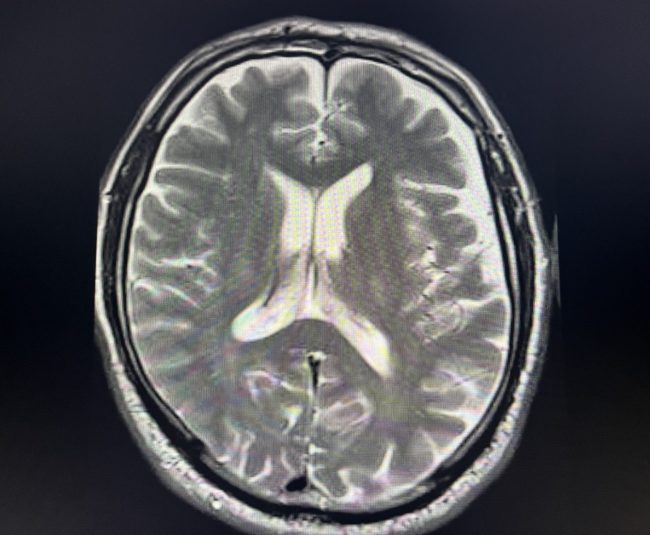

Eine ganzheitliche, personalisierte und multimodale Behandlung kann Hirnleistungsstörungen oder eine Demenz, z.B. als Folge der Alzheimer-Krankheit, wirksam vorbeugen und bessern.

Gibt es heilbare Ursachen leichter und schwerer Hirnleistungsstörungen? Ja! Deswegen ist immer eine ausführliche Diagnostik erforderlich, bevor man von einer Demenz, z.B. Alzheimer-Typ, spricht.

Unterschätzen wird leichte Hirnleistungsstörungen als Vorläufer von Alzheimer oder anderen Demenzen?